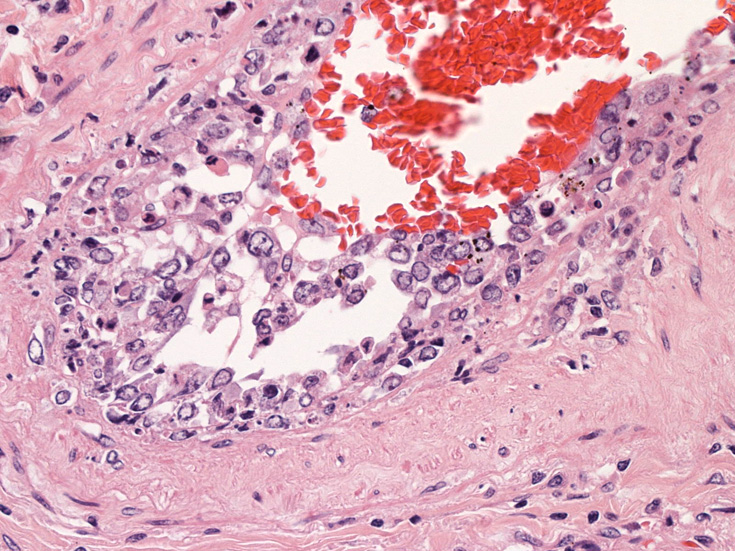

剖検病理組織所見

脳;くも膜下腔の小動脈内, 脳白質の細血管内に腫瘍細胞が充満している。